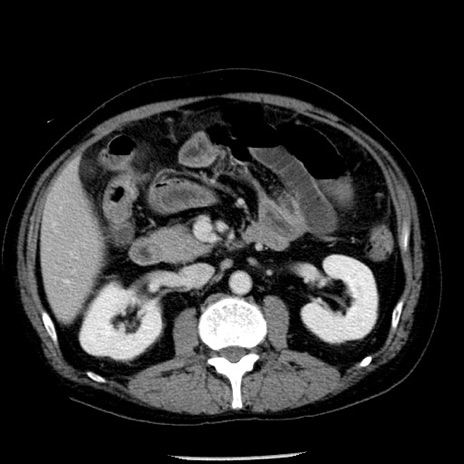

冠状断像

【症例】40歳代男性

【現病歴】2日前から胃痛あり。徐々に周期的な激痛に変化した。本日になっても激痛があるため受診。

【身体所見】意識清明、BT 38-39℃台あり、腹部:膨満、やや硬、右下腹部に圧痛あり。

【データ】WBC 8500、CRP 23.26